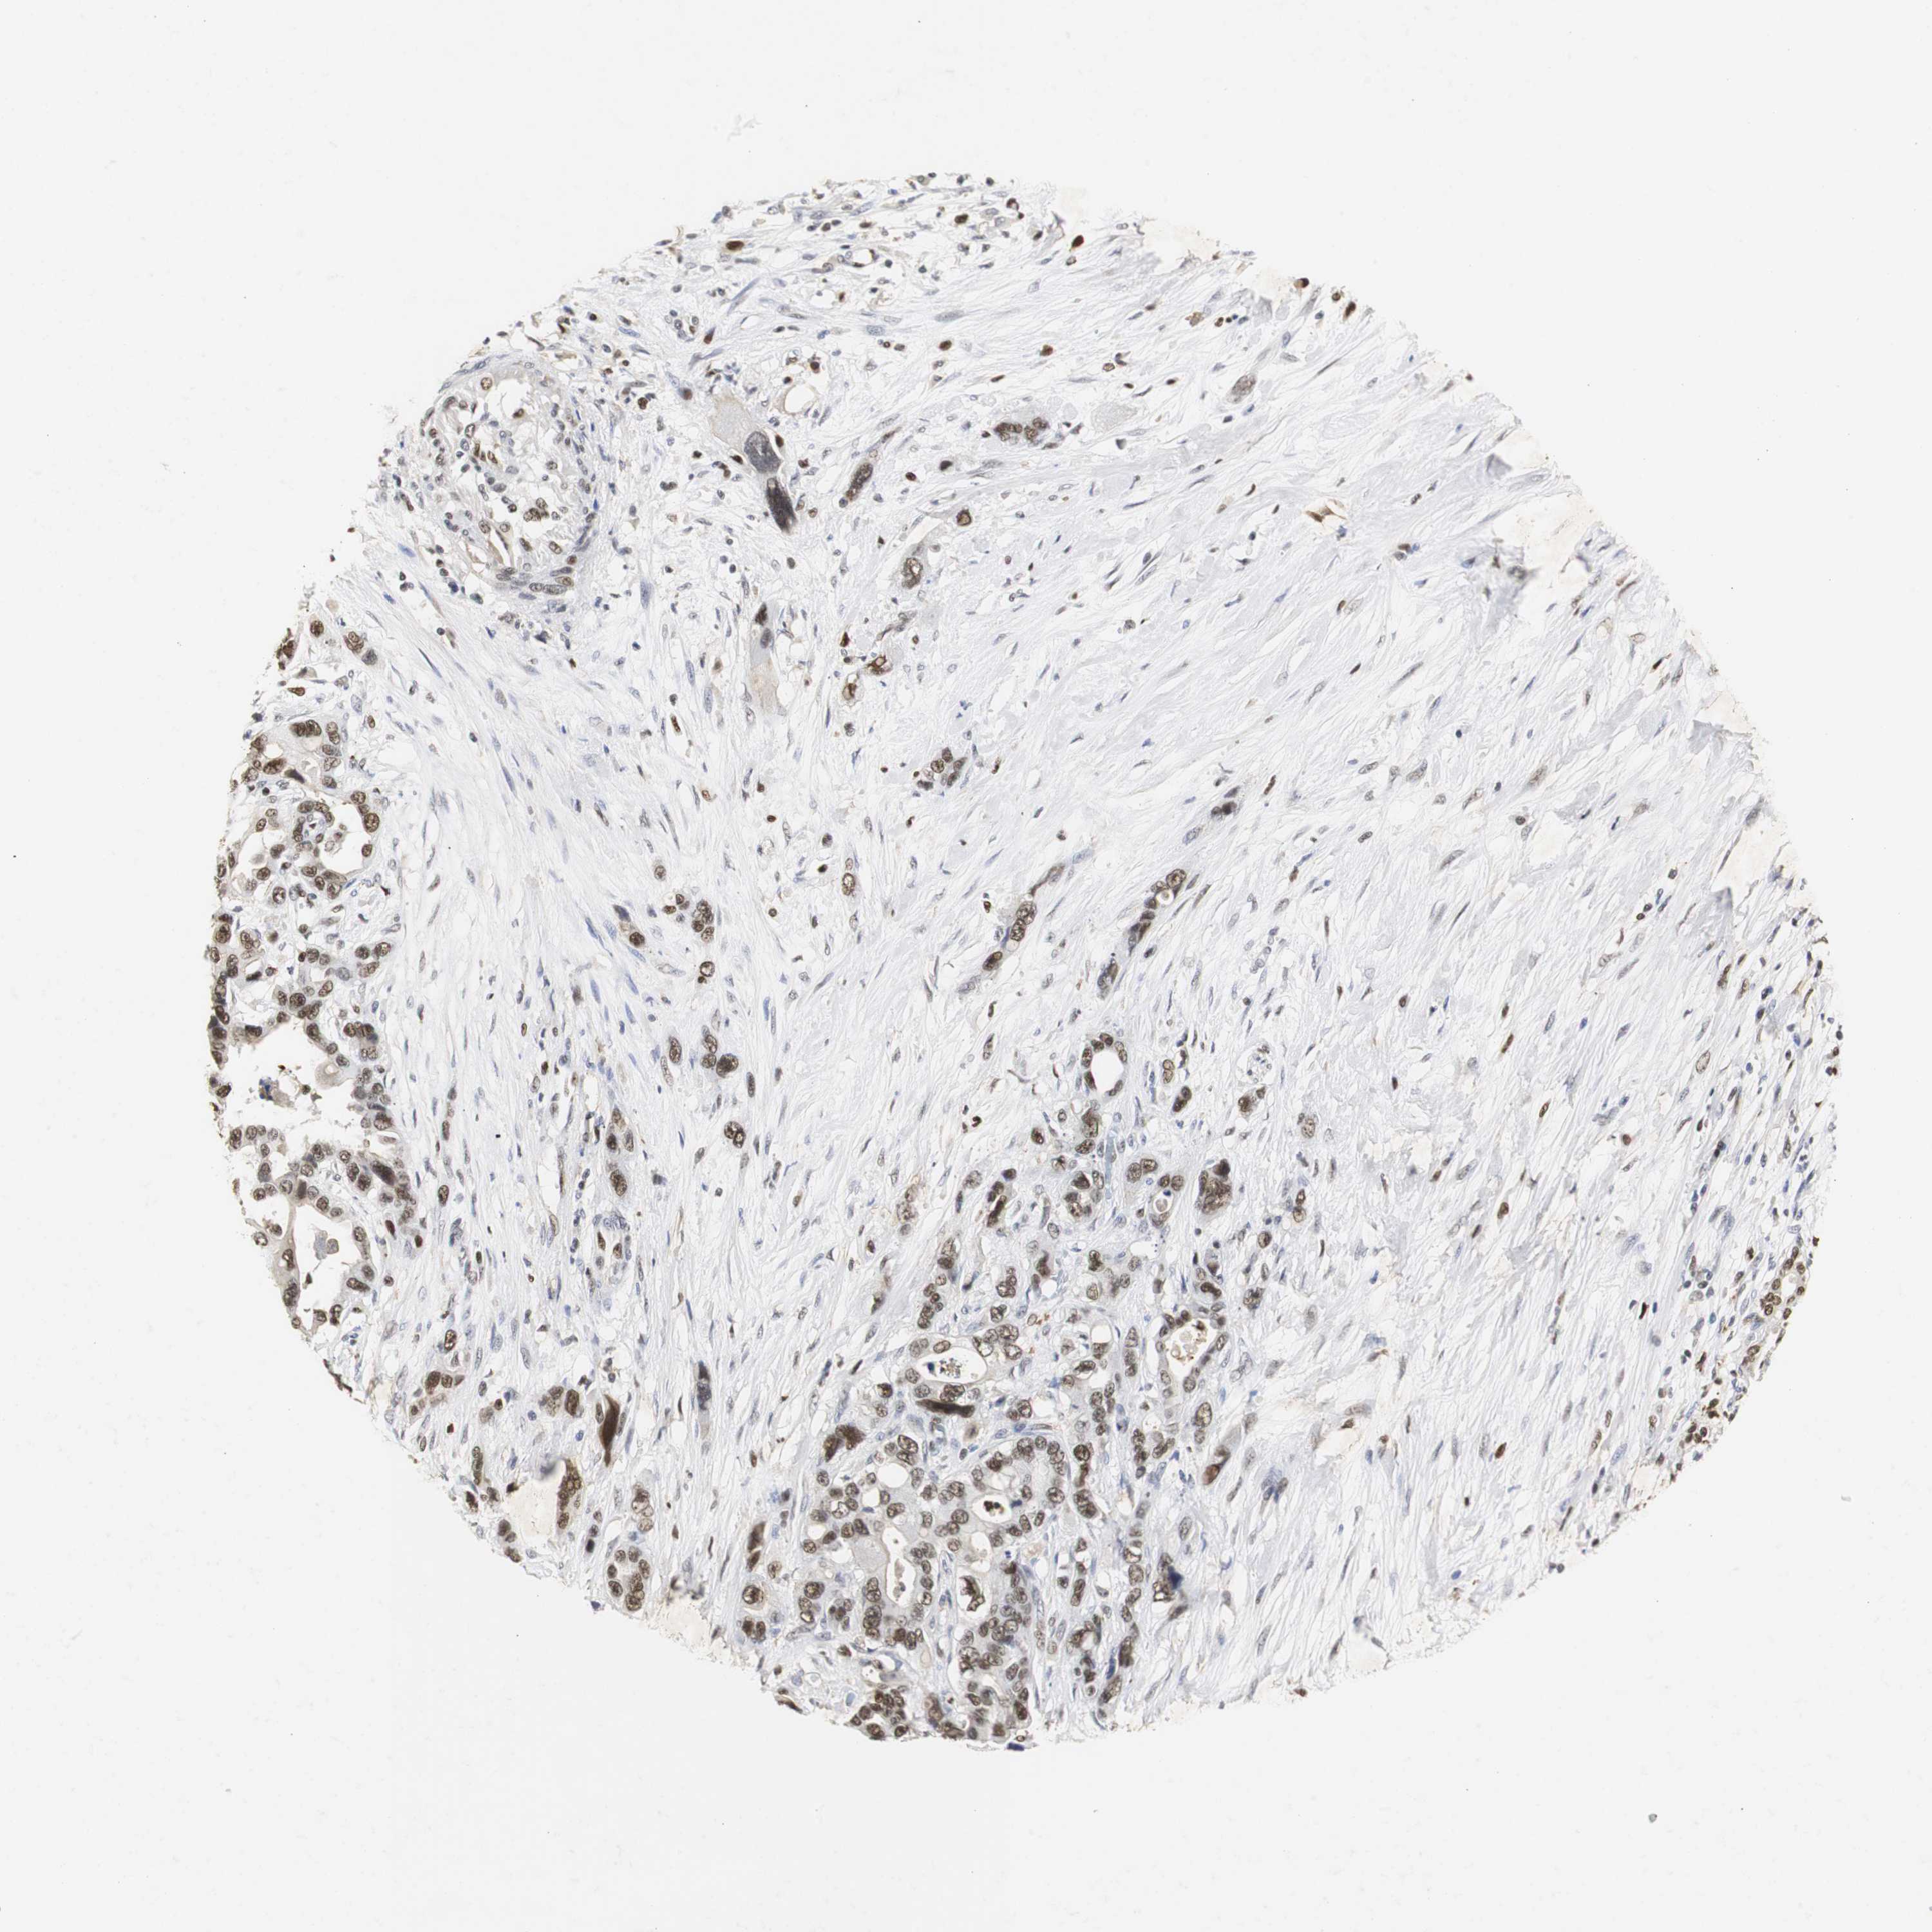

PANCREATIC CANCER - Protein expressioni

A mouse-over function shows sample information and annotation data. Click on an image to view it in a full screen mode. Samples can be filtered based on level of antibody staining by selecting one or several of the following categories: high, medium, low and not detected. The assay and annotation is described here.

Note that samples used for immunohistochemistry by the Human Protein Atlas do not correspond to samples in the TCGA dataset.

Antibody stainingi

Antibody staining in the annotated cell types in the current human tissue is reported as not detected, low, medium, or high, based on conventional immunohistochemistry profiling in selected tissues. This score is based on the combination of the staining intensity and fraction of stained cells.

Each image is clickable and will lead to virtual microscopy that enables deeper exploration of all samples and also displays staining intensity scores, fraction scores and subcellular localization as well as patient and tissue information for each sample.

Antibody HPA007072

Antibody HPA007151

Staining

High

Medium

Low

Not detected

Intensity

Strong

Moderate

Weak

Negative

Quantity

>75%

75%-25%

<25%

None

Location

Nuclear

Cytoplasmic/membranous

Cytoplasmic/membranous,nuclear

Adenocarcinoma, NOS

Adenocarcinoma, metastatic, NOS